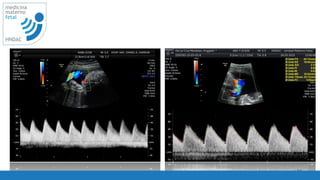

disminuir

ganancia 2D

27